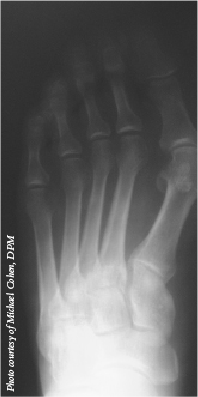

In a study involving 45 feet of patients with hallux valgus, the authors assessed a third-generation minimally invasive chevron osteotomy procedure that incorporated first- and second-generation techniques plus a distal chevron osteotomy and screw. This technique facilitated improved control and metatarsal head stabilization, according to the study. At a minimum six-month follow-up, patients’ mean hallux valgus angle had decreased from 30.54 degrees to 10.41 degrees. The study authors noted that shortening the first metatarsal did not affect clinical outcomes and patients had a low complication rate.